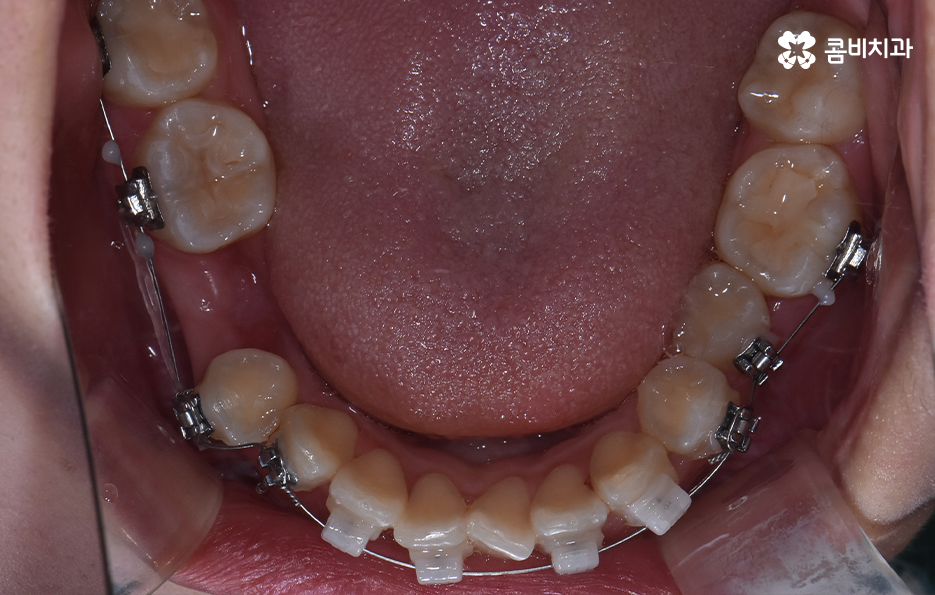

덧니는 윗니와 아랫니에 모두 있거나 앞니에 살짝 있는 수준의 덧니도 있으며 덧니가 심한 경우에는 개방교합으로 인해 입이 잘 다물어지지 않는 경우도 있기 때문에 덧니가 심한 정도에 따라서 치아교정의 계획은 세부적으로 달라질 수 있어요

덧니가 심하지 않은 경우에는 비발치로도 충분히 교정을 하는 경우도 있겠지만 덧니가 심한 경우에는 덧니 발치 교정을 통해서 치료가 진행되는 경우가 많이 있는데요. 그 이유는 치아교정의 원리를 생각하더라도 치아를 재배치하기 위해서는 기존의 치아가 움직일 공간이 필요한데 덧니는 치열이 이미 완성되고 있는 상태에서 치아가 나올 공간이 부족하여 덧니가 되는 경우가 많다는 점에서도 치아의 이동 공간을 확보하기 위한 발치가 필요할 수 있는 거예요